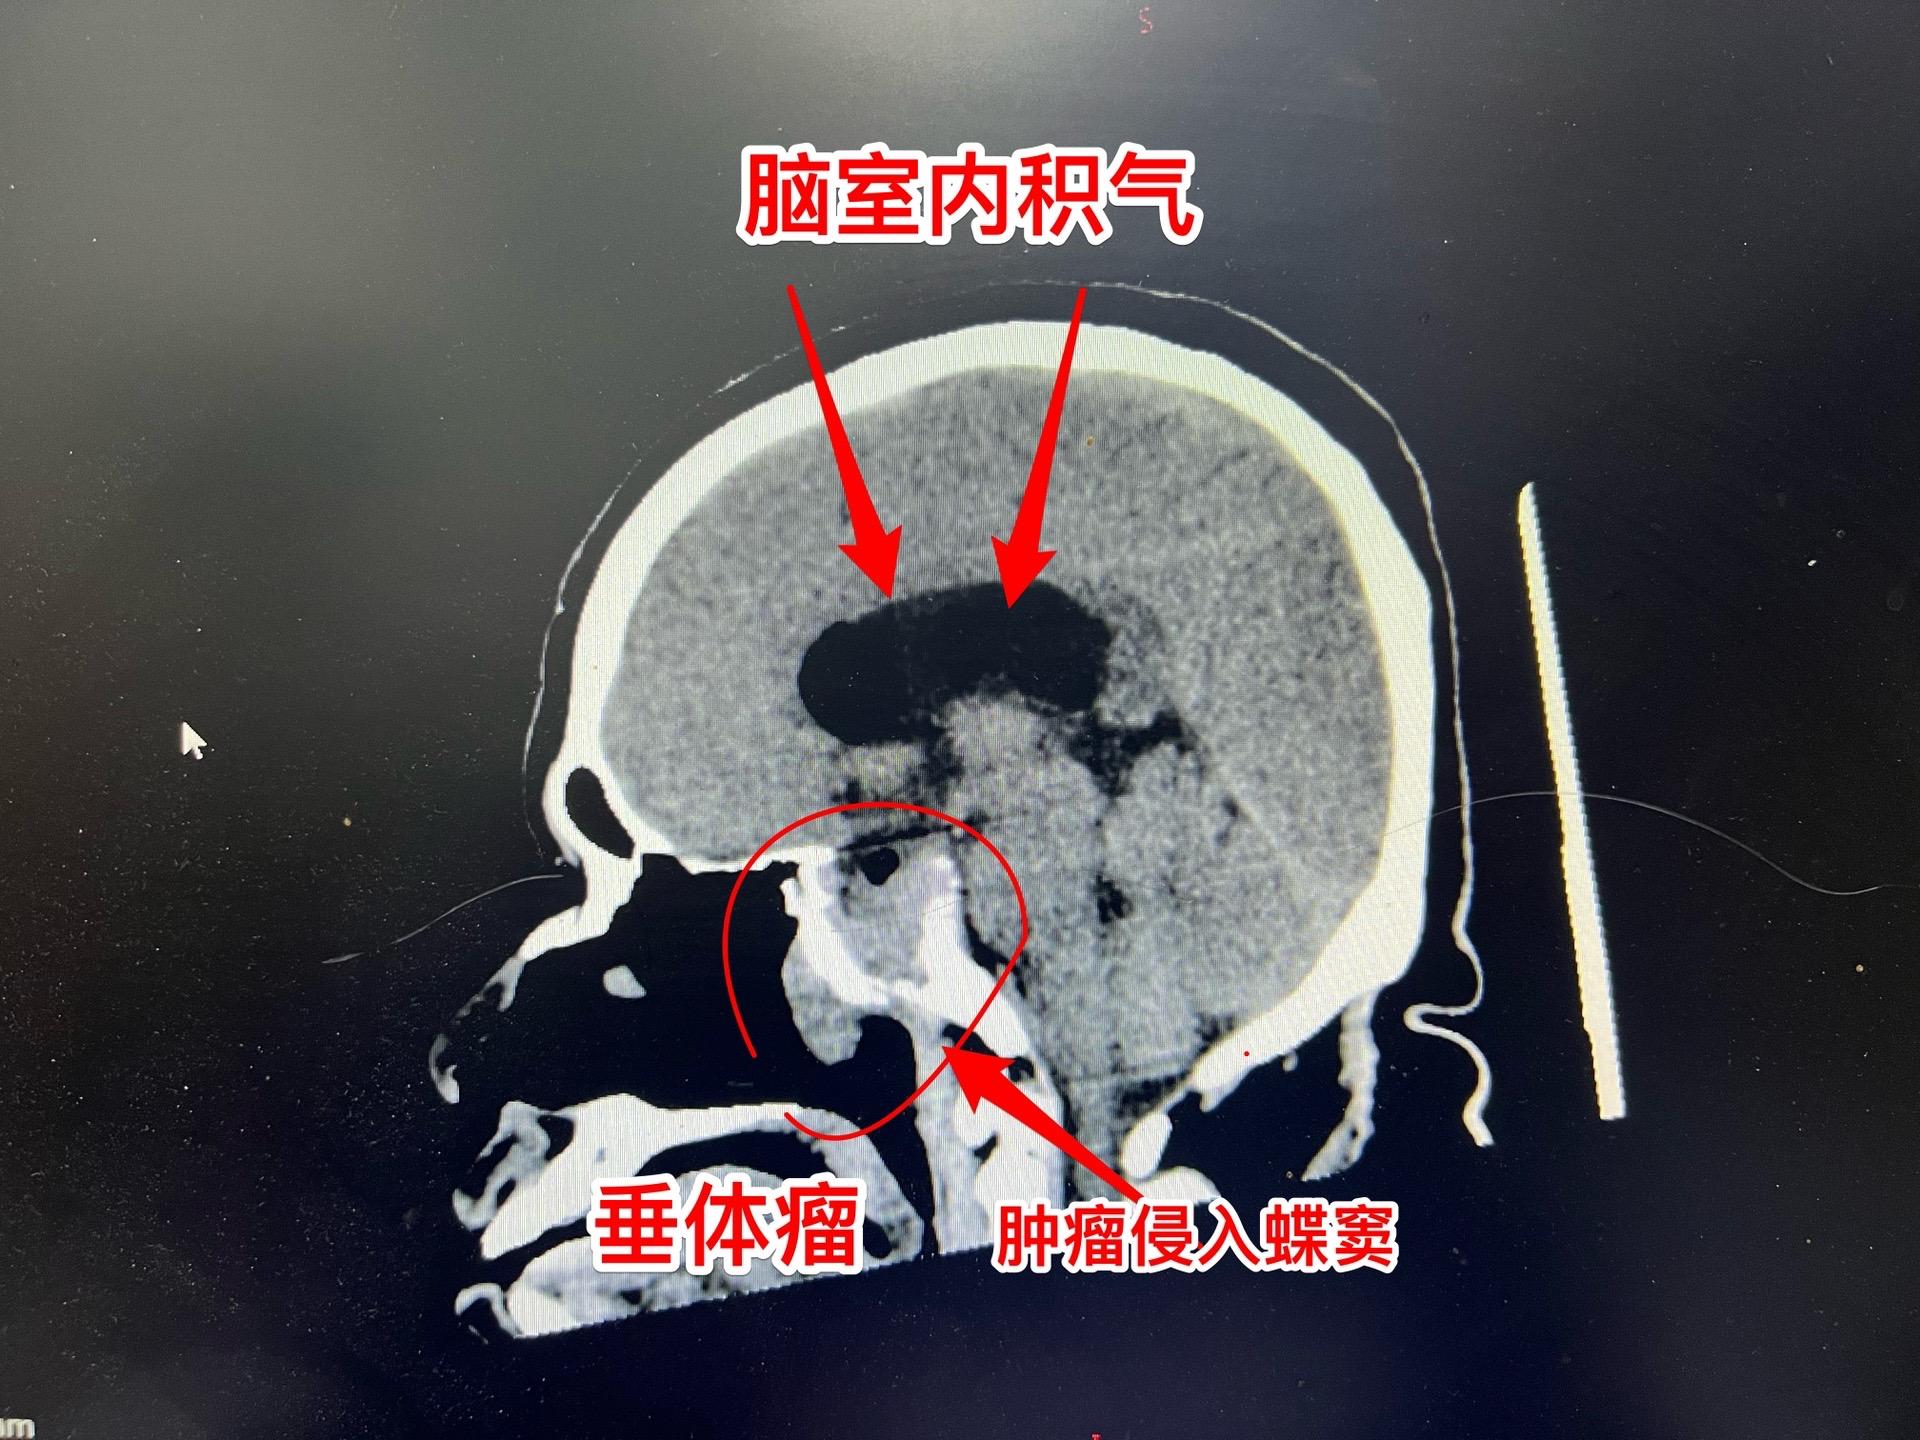

吃药能让垂体瘤消失?这不是传说。垂体瘤中有一种特殊的瘤叫泌乳素瘤,可以通过吃药就化掉了!这不是传说!最常用的药叫溴隐亭! 但是,切记:如果停药了,肿瘤又会长出来的! 这个51岁的承德市男性,3年前因视力下降到医院检查发现了垂体瘤,经过化验泌乳素,被确诊为泌乳素瘤。口服溴隐亭这个神药,肿瘤变小了,吃药两年后病人因为头晕、行走困难而停药。停药一年后肿瘤又复发了,肿瘤体积很大,侵蚀了垂体窝骨质进入蝶窦内! 2024年10月25日在我科复查泌乳素,显示泌乳素水平远远